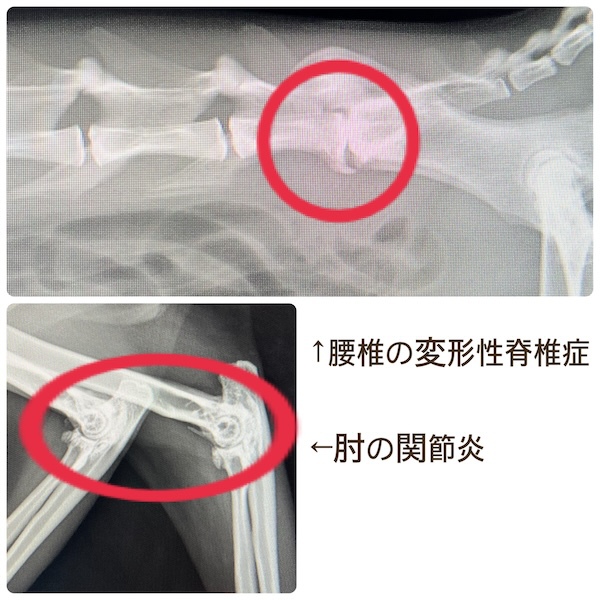

猫の関節炎(2026/01/05)

猫の変形性関節症・変形性脊椎症は、中〜高齢猫の60-90%が抱えているとされる関節炎のひとつです。しかし、活動量が落ちていても、年のせいだと感じたり、はっきりとした症状が出ないケースもあるため、飼い主が気付かないことも多い病気です。診断にはレントゲン検査を用い、手根(手首)や肘、肩、膝関節及び脊椎に炎症がないかを確認していきます。治療には、疼痛の緩和を目的とした消炎鎮痛剤(内服薬、注射薬)の他、温熱療法や関節保護作用のあるサプリメントを推奨することがあります。段差の昇り降りを躊躇う、おもちゃで遊ばなくなったなど、活動性に変化が見られる場合はお気軽にご相談ください。

変形性脊椎症(2025/12/08)

変形性脊椎症は、身体を支えている背骨(脊椎)が年齢とともに少しずつ変形してしまう病気です。多くは無症状なためレントゲン検査で偶然見つかることも珍しくありません。しかし、変形した脊椎が神経を圧迫することで痛みや歩行異常が現れることがあります。椎間板の変性や加齢による椎体間の不安定性が原因と考えられています。症状が見られる場合は、鎮痛剤で痛みを和らげたり、温熱療法などの理学療法で筋肉の緊張をほぐしながら経過を見ていきます。最近活動量が減ってきた、歩きにくそうにしている、などの変化は病気のサインかもしれません。なにか気になる症状があればお気軽にご相談下さい。